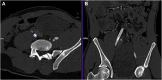

Mechanical valve leaflets have the potential to detach and migrate to unintended locations, leading to life- and limb-threatening situations. We report a unique case of a dislodged mechanical aortic valve leaflet in the right iliac artery bifurcation after a redo mitral valve replacement. This was promptly recognized by input from a multidisciplinary team, allowing immediate correction of the aortic valve insufficiency followed by staged retrieval of the dislodged leaflet to avoid vascular complications. This case highlights the importance of a multidisciplinary team in decision-making and timely intervention. Further research is needed for better understanding of risk factors and prevention strategies.